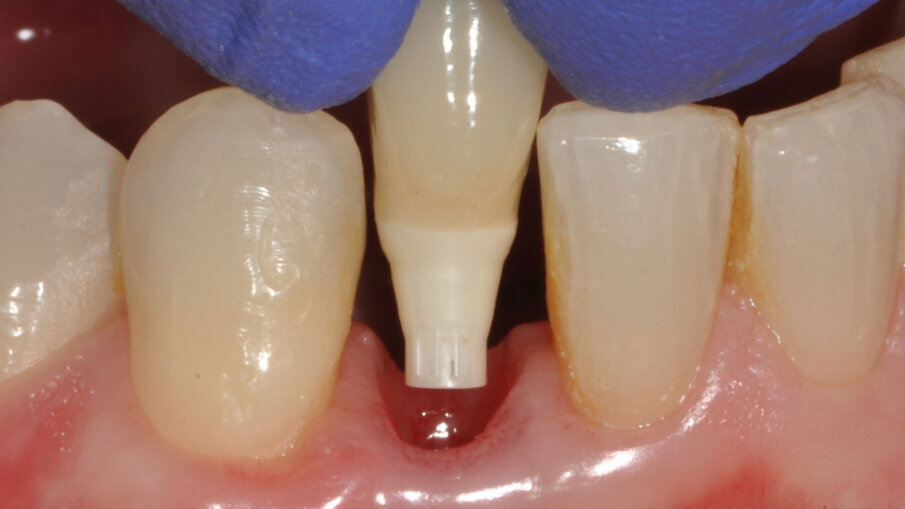

Zavedení implantátu